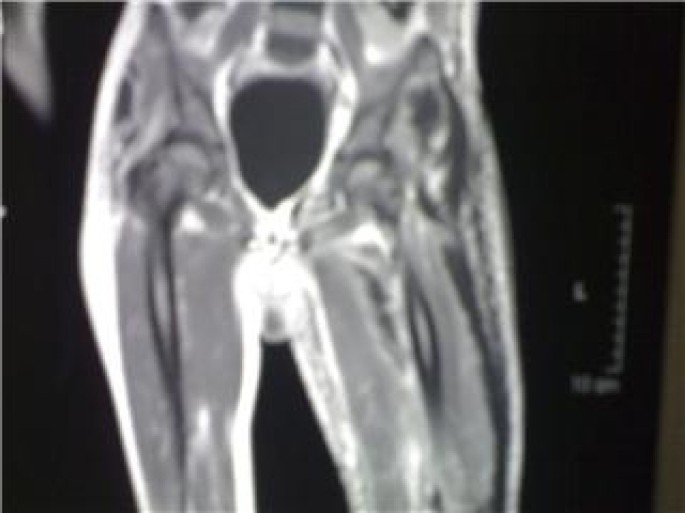

Plain x ray of both hips and thigh revealed soft tissue edema of left thigh and normal left hip joint, figure 2. Chest radiograph was normal. Doppler ultrasonographic examination of the left lower extremity revealed no abnormality. MRI of the left thigh revealed extension of inflammation along the fascial plains, figures 3.

Magnetic resonance imaging (MRI) has the highest sensitivity (93–100%) for diagnosing NF. NF exhibits high signal intensity on T2-weighted images by MRI with hyperintense signal corresponding to fluids associated with NF. Using MRI, Rahmouni et al. were able to identify necrotizing soft-tissue infections which warrant immediate surgical intervention from non-necrotizing cellulitis, which can be treated medically [14].